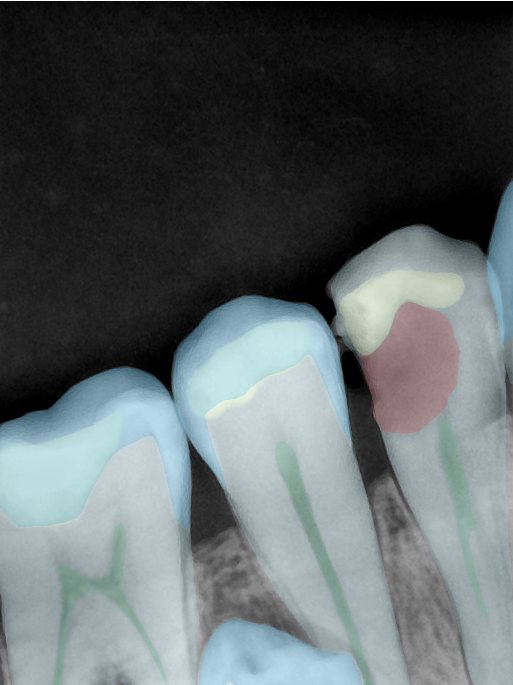

CR/DR 牙齿分割阶段记录

当前进展

- 完成了 CR/DR 牙齿相关分割训练

- 当前结果已经达到阶段预期,但仍有细节问题需要继续处理

相关测试

遇到的问题

- 训练过程中出现过 mask 下移问题

- 部分结果会出现 box 填充异常

- mask 边缘仍然有比较明显的锯齿感

第二版算法问题测试